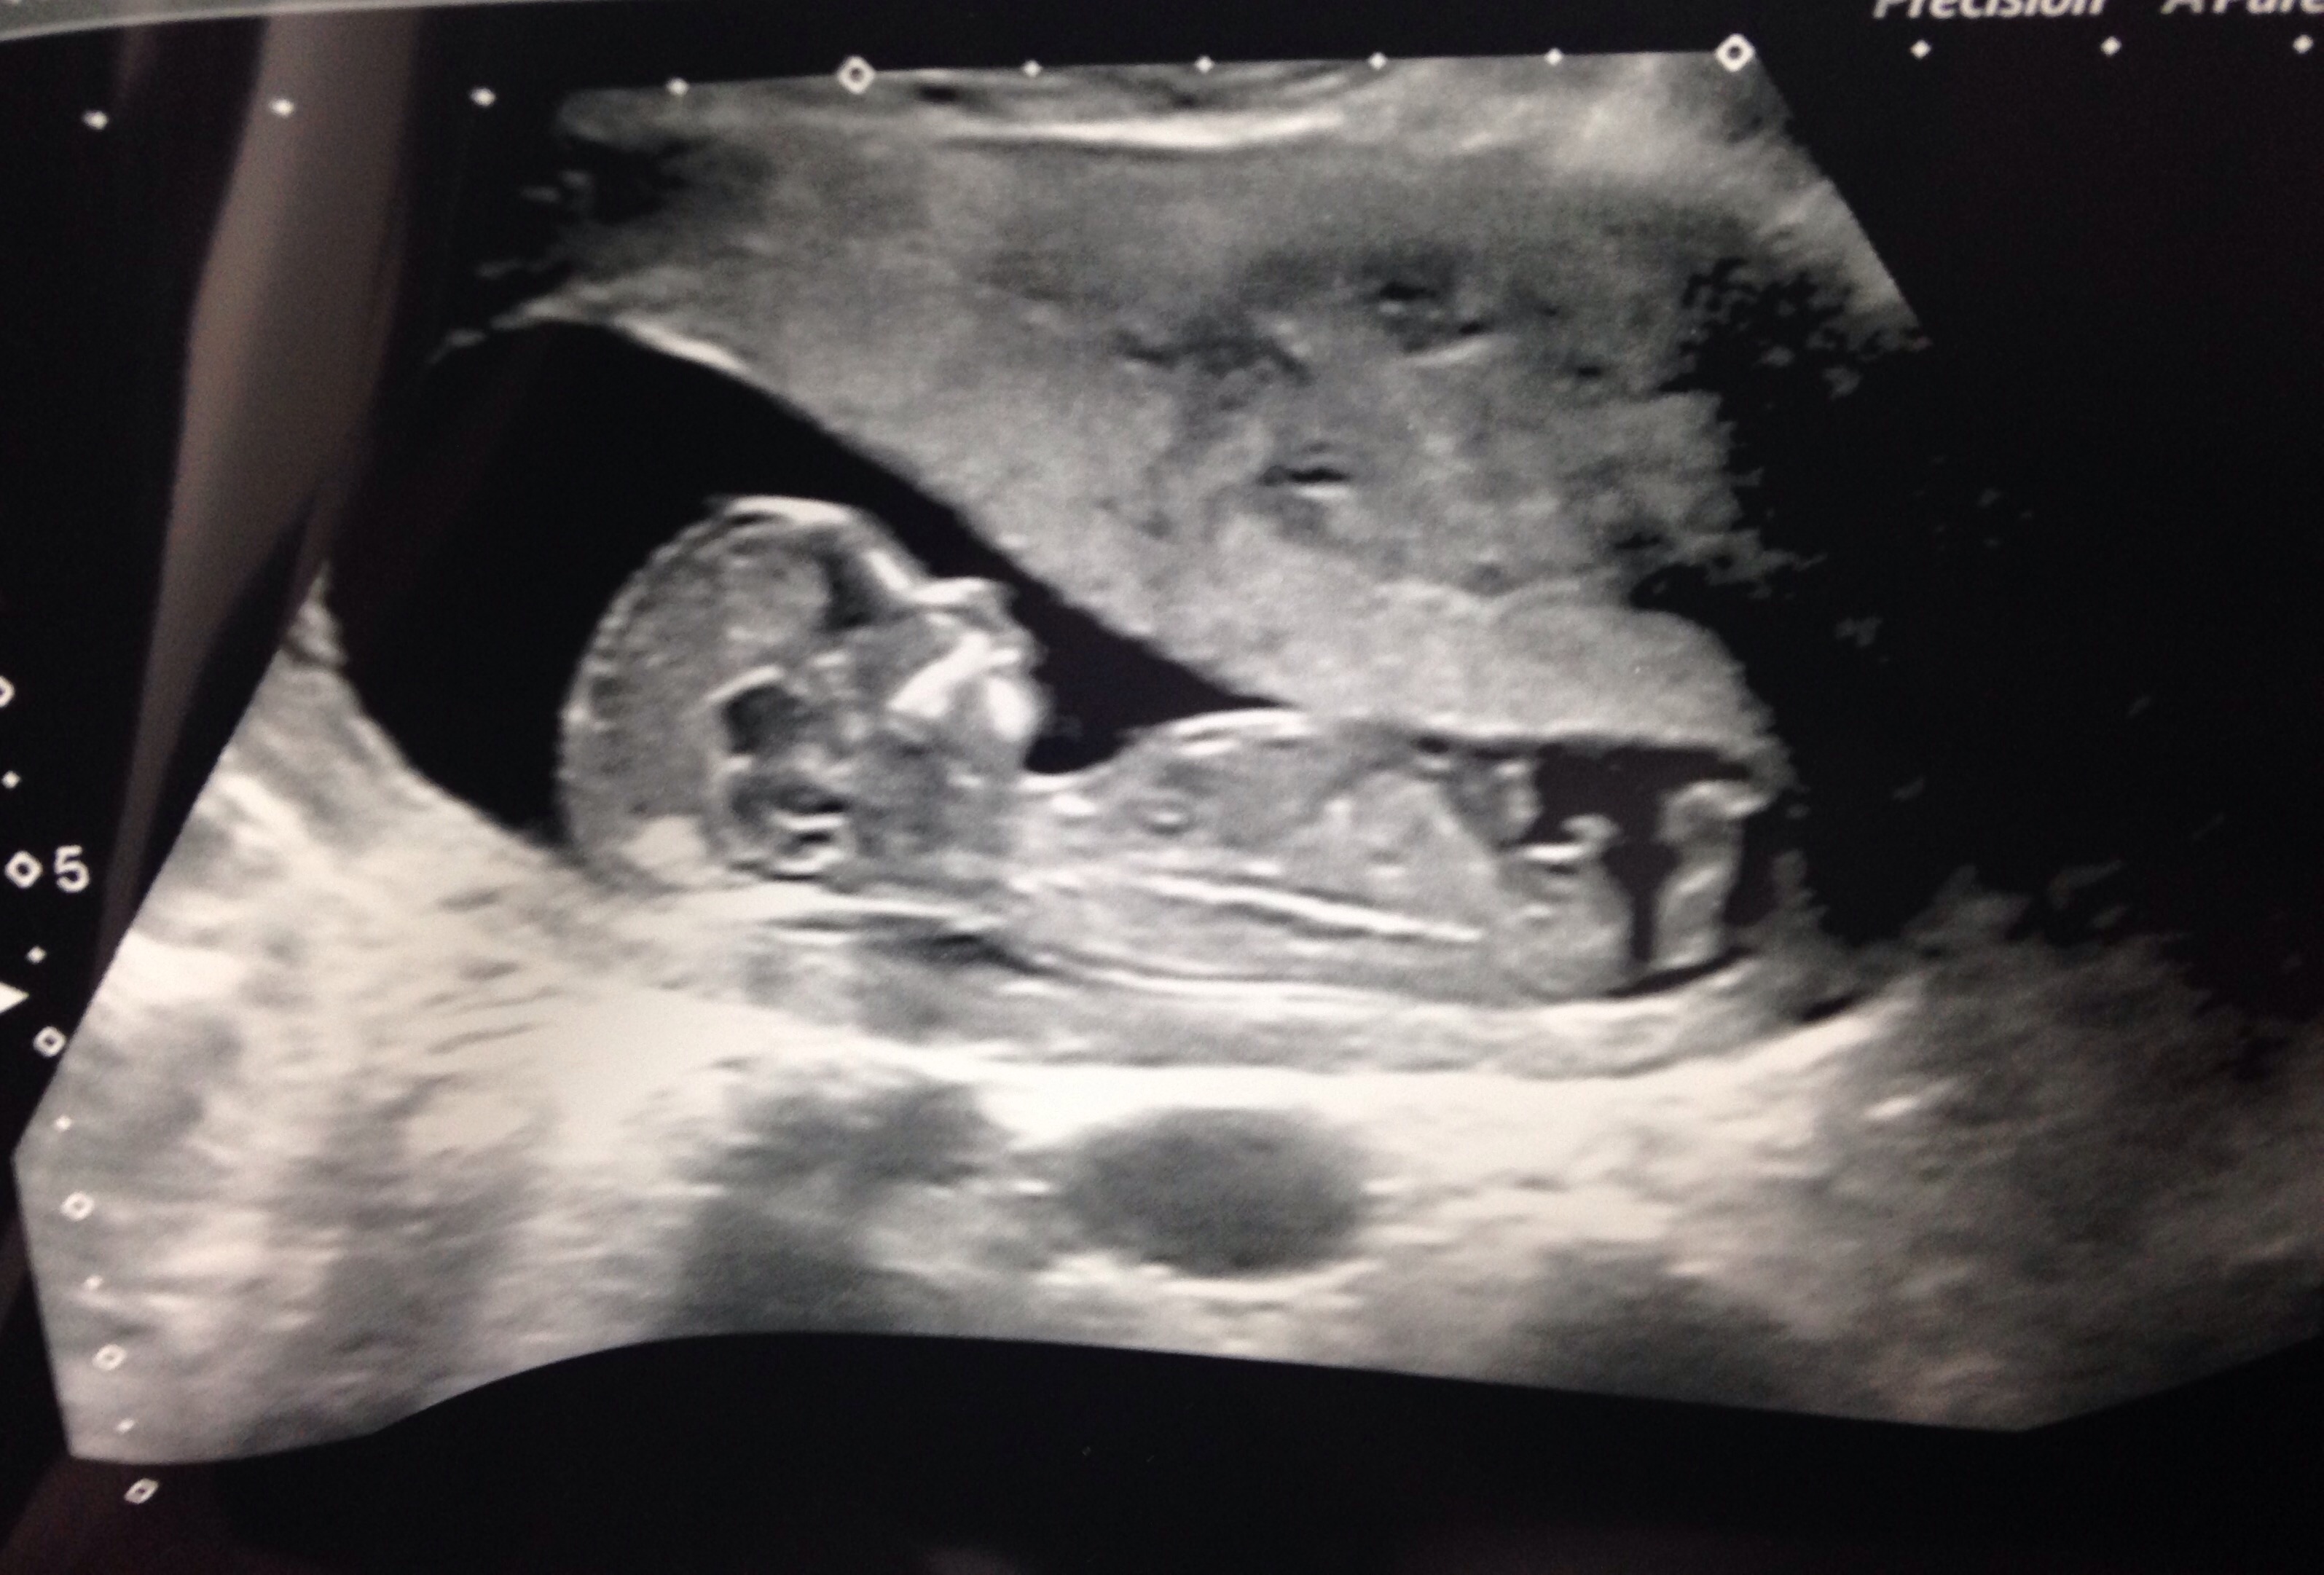

Attachment 23995Hi guys! Gender scan tomorrow at 16+6! (Anticipation took over lol!!!) this scan is 13+1.. My babies nub is very flat (girly) but has something on the end (boyish) can anyone shine light on this? I always thought the nub theory was the 'angle of the dangle?' Does my babies nub go against this? Place your guesses guys I will update you all when I find out! Thank you all xxx